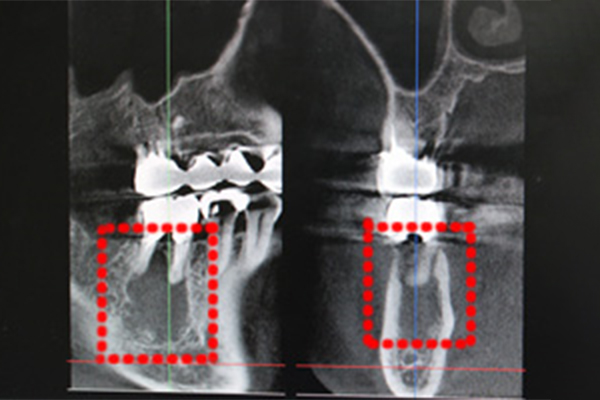

CGF治療初診時

歯の根の下に大きな膿のかたまりができて骨がなくなっています。歯を抜歯して患者様の血液から採取したCGFを骨補てん材と共に埋入、骨ができるのを待ちます。